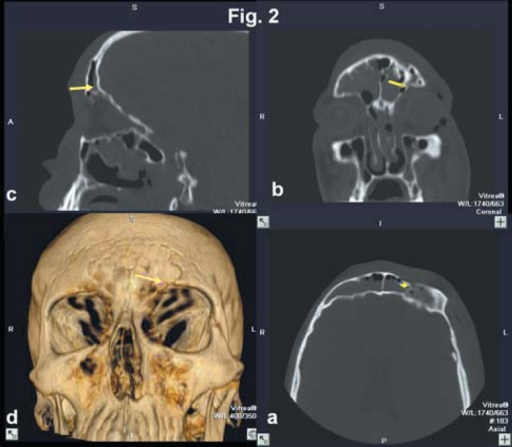

진단 (Diagnosis)

- CT (coronal + axial): 골절 위치, 크기, 감돈 조직 확인